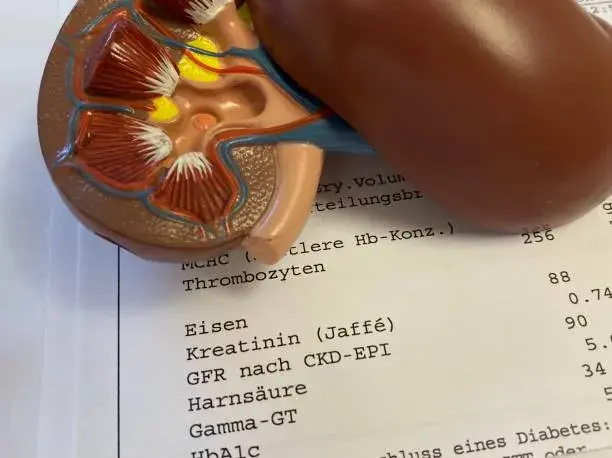

Qual o limite para o consumo de proteína sugerido pelo KDIGO de DRC 2023?

Qual o limite para o consumo de proteína sugerido pelo KDIGO de DRC 2023?

Existe muita controvérsia quanto a restrição proteica nos pacientes com DRC. Confere a atualização do KDIGO 2023 sobre DRC.